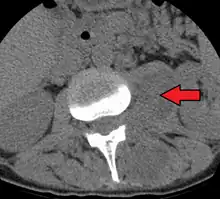

Psoas muscle abscess

Psoas abscess is a collection of pus in the iliopsoas muscle compartment.[1][2] It can be classified into primary psoas abscess (caused by hematogenous or lymphatic spread of a pathogen) and secondary psoas abscess (resulting from contiguous spread from an adjacent infectious focus).[2]

| Paraspinal abscess in the psoas muscle | |

Psoas abscess may be caused by lumbar tuberculosis. Owing to the proximal attachments of the iliopsoas, such an abscess may drain inferiorly into the upper medial thigh and present as a swelling in the region. The sheath of the muscle arises from the lumbar vertebrae and the intervertebral discs between the vertebrae. The disc is more susceptible to infection, from tuberculosis and Salmonella discitis. The infection can spread into the psoas muscle sheath.[3]